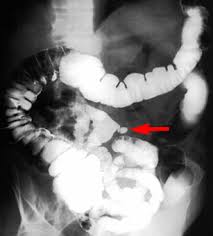

| Diverticules de l'intestin .

Image de trois diveticule le long de l'intestin se

voyait si net sur cliche de face du transit baryte

avec tech compression dose de l'abdomen . |